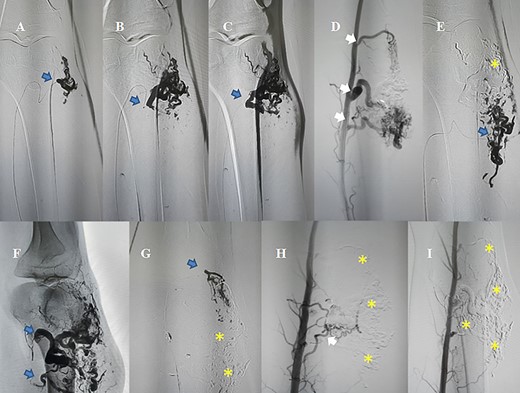

AVM embolization was performed through antegradely femoral approach; white arrows: the existence of feeding arteries need to be occluded; blue arrows: nidus and feeding arteries are being occluded by NBCA/Lipiodol; (asterisk) nidus and feeding arteries were totally occluded.

In the beginning, we recognized that this AVM has 3–4 main parent arteries (Fig. 1).

The patient had undergone an embolization (Fig. 2) and a surgical excision after 4 days (Fig. 3). The mean volume of injected NBCA/Lipiodol 12.5% was 15-20 mL. Clinical symptoms were medium pain and swelling. These symptoms decrease gradually and disappear within 4 days. No long-term peripheral circulation or pulmonary deficit was noted during the period of follow-up.